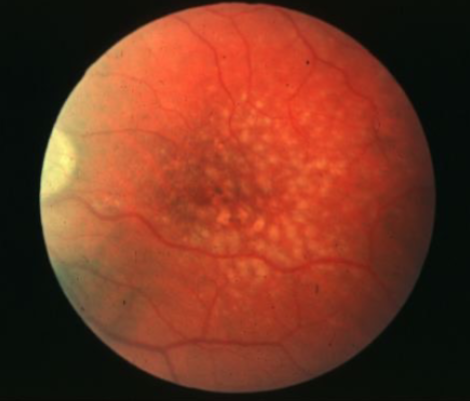

drusen

drusen

soft drusen

soft drusen

soft drusen

soft drusen

reticular pseudodrusen